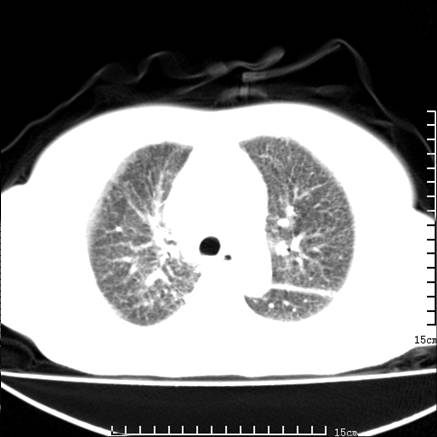

女,王某,58岁,咳嗽三个月余,基层医院二个月前诊为肺结核,用抗结核药二个月无明显疗效。

双肺继发型tb,心功能不全并肺淤血、心包、双侧叶间裂积液,肺大泡,右下胸膜肥厚钙化。

肺窗真难看,建议重做!